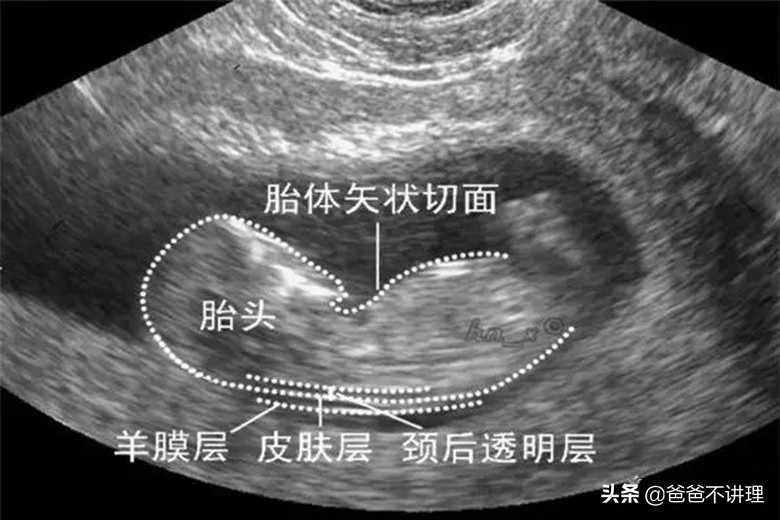

B超测量胎儿NT增厚,对B超医生是一种考验。如果胎儿一直动个不停,或者胎儿的位置不好不方便医生观察和测量,那么NT值肯定要受到影响。所以做NT要取胎儿正侧位,连续测量3次然后取NT最大值才比较准确。